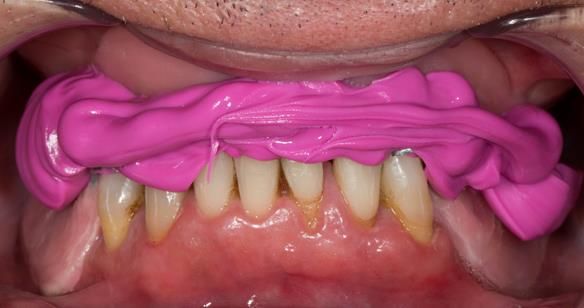

This 52 year old man was referred to me from his general dental practitioner in 2018.

10 years prior to consultation the patient's general dentist diagnosed periodontitis and referred him to Manchester Dental Hospital. He received a treatment plan to manage the periodontitis. Unfortunately, this was not acted on. Four years ago gaps developed between the upper front teeth. Orthodontic treatment was provided to align the teeth. A bonded retainer was fitted onto the upper front teeth. Approximately one year prior to consultation with me the patient noticed the teeth moving again. He consulted his orthodontist, who advised no further orthodontic treatment. One month prior to the consultation with me the upper left central incisor fell out whilst eating.

- Generalised periodontitis; stage IV grade C: currently unstable, risk factors: smoker.

- The remaining maxillary teeth had hopeless prognosis in the short term. They exhibited 80 - 100% alveolar bone loss with increased mobility (Grade 2 - 3).

- The lower right second premolar and lower left first premolar (LR5 LL4) had hopeless prognosis in the short term. They exhibited 80 - 100% alveolar bone loss with grade 3 mobility.

- The remaining mandibular teeth had approximately 30 - 50% alveolar bone loss with grade 1 mobility.